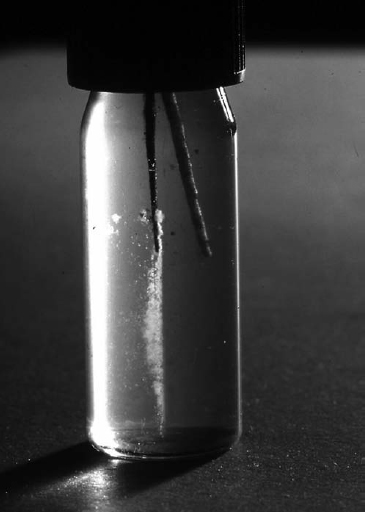

When a sensitive technique is used80 the chances are optimized for bacterial recovery. For example, where three samples are taken and no growth is seen with one sample the others can be used as backup and check of the first sample. An ‘enrichment’ medium, fluid thioglycolate medium (FTM), was used so that if colonies did not appear on the plates, new plates were inoculated from the other PYG broth and the FTM. If none are positive for bacteria, one can be more assured of the veracity of a negative result. Even the application of paper points must be done with utmost care to maximize recovery of fluid from the root canal. Figure 7 shows two paper points from the same canal. One is negative and the other is positive for bacteria, because the left one is thinner and reached further apically in the canal to capture bacteria. The light microscopic view of a sectioned tooth root apex shown in Fig 5 illustrates where bacteria may be located and how they can escape recovery if a paper point does not reach the full canal length.

Fig 7. Two paper points from the same canal. The right one is negative for bacteria, whereas the left paper point is thinner and has reached further apically in the canal to recover bacteria.